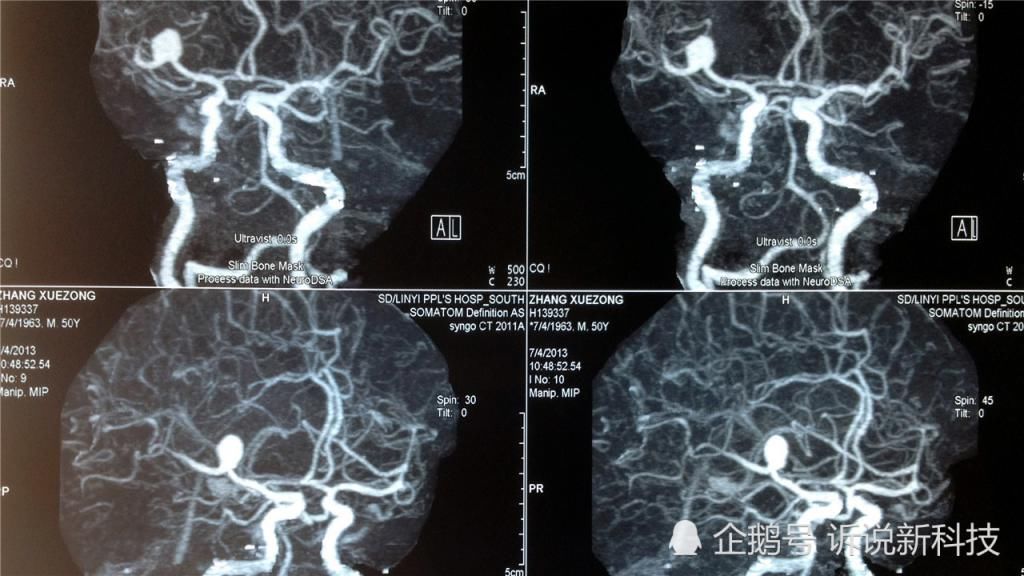

根据研究发现,大脑是人体结构中最神秘的存在,它的精密多远超最先进的计算机。初步估计,大脑中存在着数百亿个神经元,大部分人的大脑开发却只有6%,哪怕是智商极高的爱因斯坦,他的大脑也只开发了10%。人类大脑的开发,到底都受哪些因素的制约?为什么会出现只开发1成的情况呢?